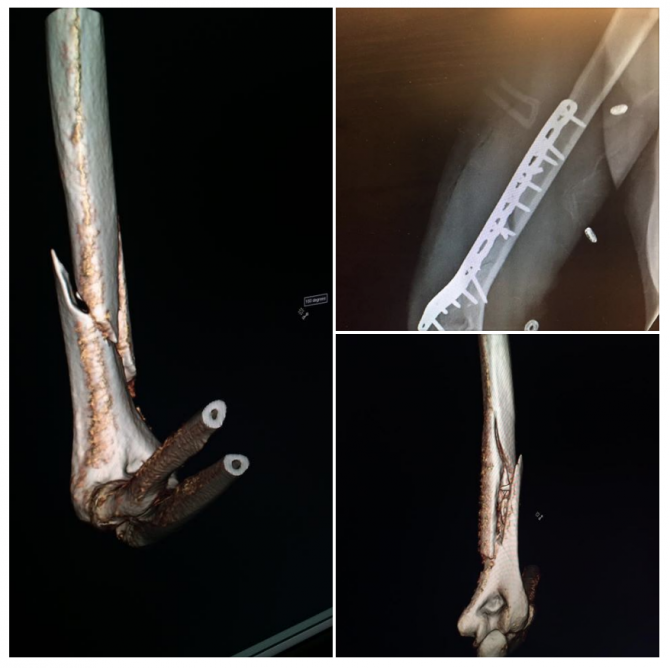

В своем посте на Facebook она заявила, что сломала кость правой руки и перенесла операцию в четверг вечером. Врачи клиники Вейл, куда она была доставлена, использовали пластины и винты, чтобы поставить кость обратно на место. Операция прошла успешно.